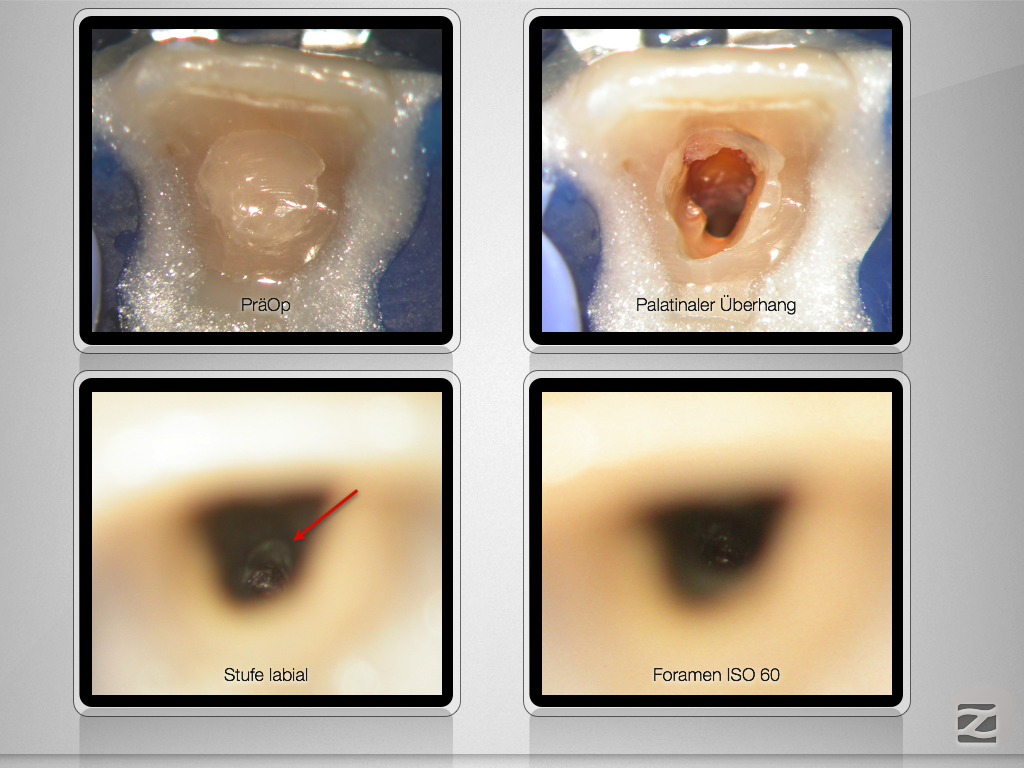

21D.002

Tücke des Details